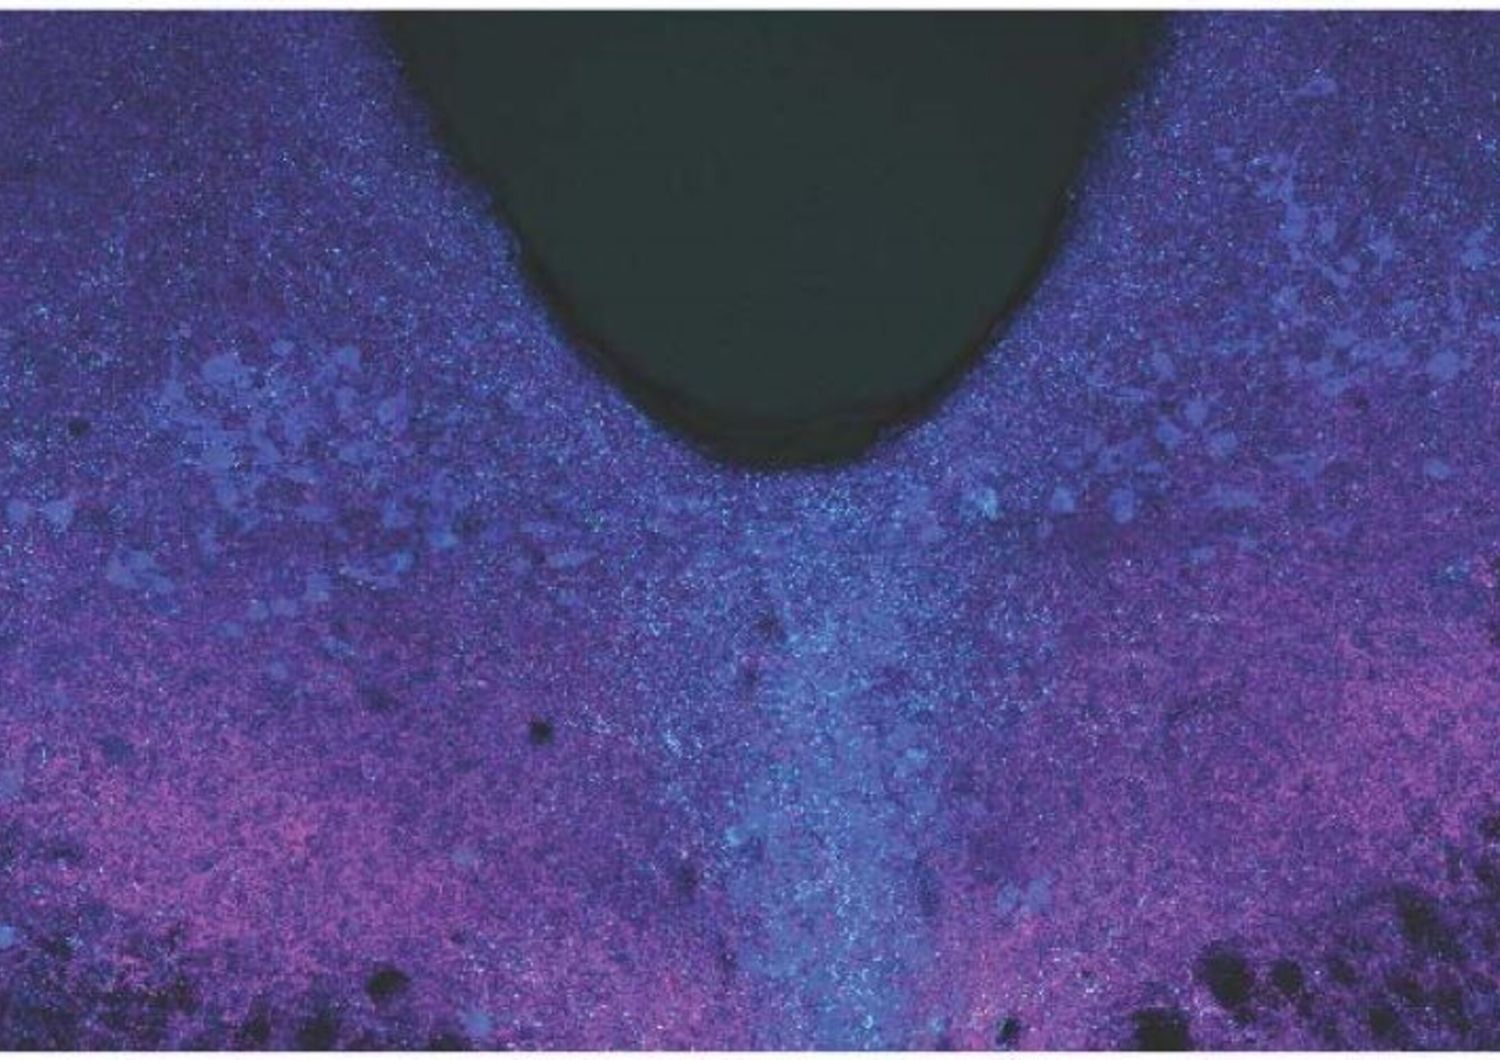

AGI - Identificare i cambiamenti nella biochimica del cervello e mappare mappato i circuiti neurali che causano un’esperienza di paura generalizzata potrebbe contribuire allo sviluppo di trattamenti specifici per chi soffre di stress cronico e attacchi di panico. A compiere un passo in avanti verso questa direzione uno studio, pubblicato sulla rivista Science, condotto dagli scienziati dell’Università della California a San Diego. Il team, guidato da Hui-quan Li e Atkinson Nick Spitzer, ha utilizzato un modello murino per individuare i meccanismi che inducono il cervello a produrre sentimenti di paura in assenza di reali minacce. Il nostro sistema nervoso, spiegano gli esperti, è naturalmente predisposto per provare paura, che rappresenta un meccanismo di sopravvivenza fondamentale per rispondere alle situazioni di pericolo. In assenza di minacce tangibili, però, la paura può essere dannosa per il nostro benessere, specialmente se si manifesta in modo continuato, intenso e frequente. Sperimentare questa generalizzazione della paura può provocare condizioni debilitanti di salute mentale, come il disturbo da stress post-traumatico (PTSD). Nell’ambito del nuovo lavoro, gli scienziati hanno scoperto i neurotrasmettitori alla base della paura generalizzata indotta dallo stress. Il gruppo di ricerca ha analizzato un’area del cervello chiamata rafe dorsale, in un modello murino. Gli autori hanno scoperto che lo stress acuto induce un cambiamento nei segnali chimici nei neuroni, passando dai neurotrasmettitori eccitatori “glutammato” a quelli inibitori “GABA”. “I nostri risultati – osserva Spitzer – forniscono importanti informazioni sui meccanismi coinvolti nella generalizzazione della paura. Comprendere questi processi a questo livello di dettaglio molecolare ci aiuterebbe a sviluppare interventi specifici per chi soffre di disturbi ad essi correlati”. Successivamente, il team ha esaminato il cervello umano post-mortem di individui che avevano sofferto di disturbo da stress post-traumatico, rilevando la presenza di un meccanismo simile a quello animale. Infine, gli esperti sono riusciti a inibire la via di trasmissione iniettando nei modelli murini virus adeno-associato (AAV) per sopprimere il gene responsabile della sintesi del GABA. I topolini trattati con fluoxetina, il principio attivo del Prozac, sembravano in grado di prevenire il cambiamento del trasmettitore e la conseguente insorgenza di paura generalizzata. I ricercatori hanno quindi dimostrato le connessioni dei neuroni che commutavano il trasmettitore con le regioni del cervello collegate alla generazione delle risposte alla paura. “Queste nuove conoscenze – conclude Spitzer – potrebbero aiutarci a progettare interventi mirati e specifici per i singoli pazienti”.